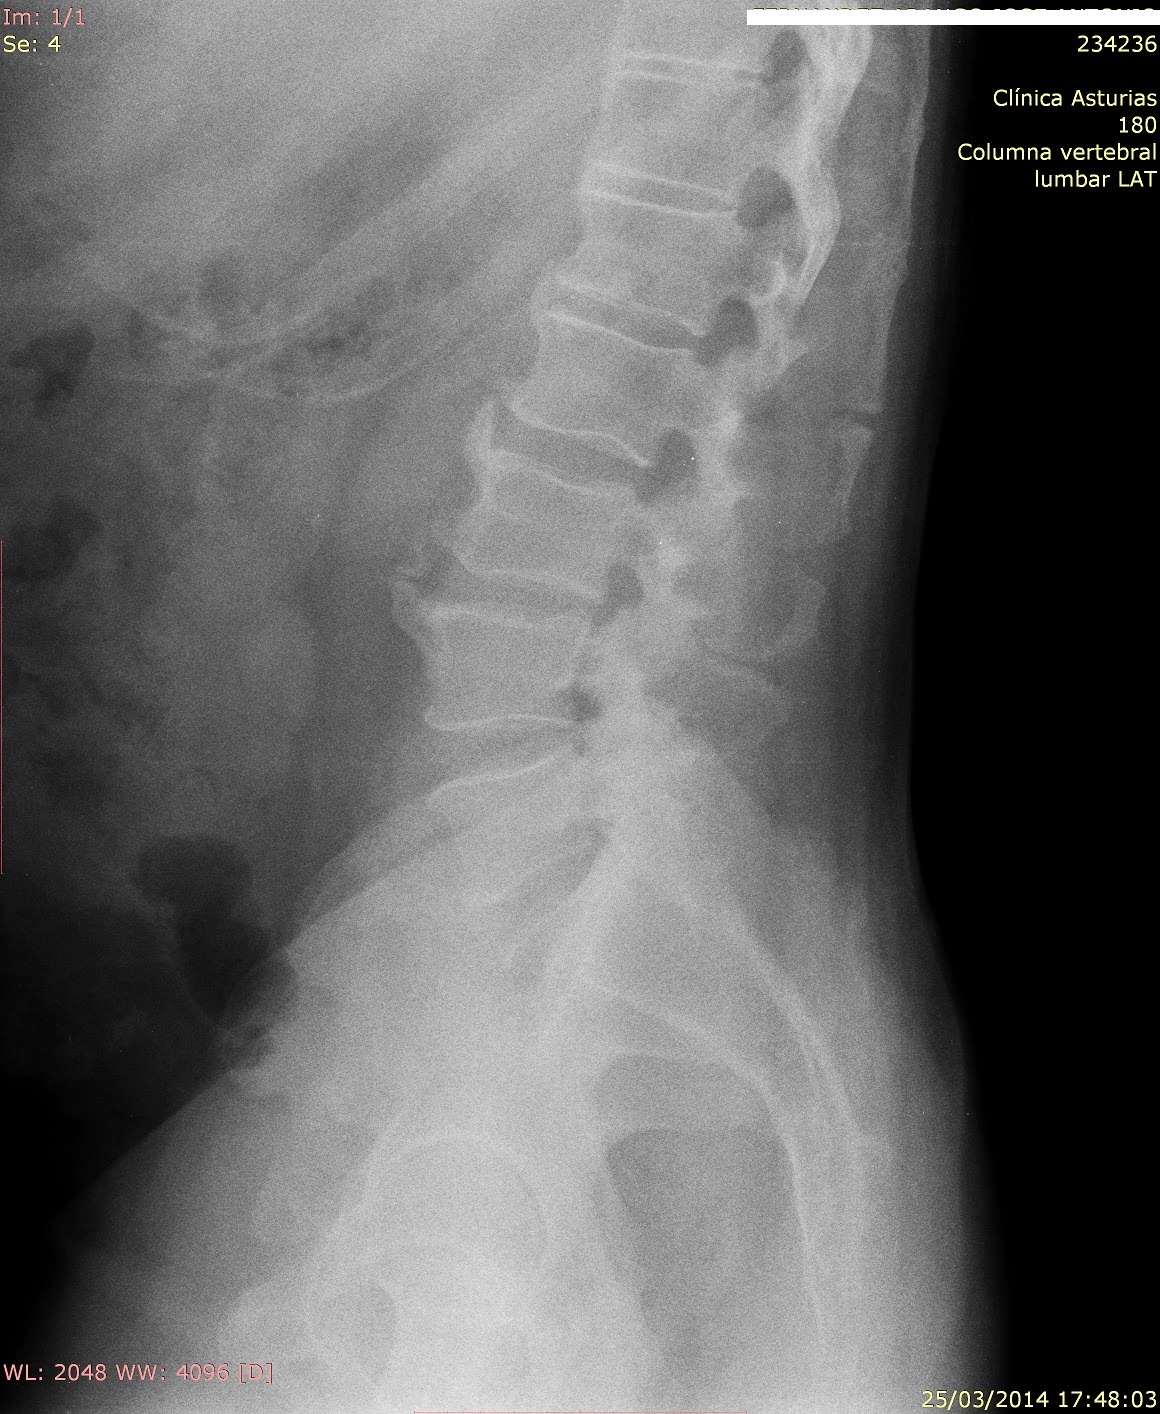

Complicaciones de las artrodesis de columna. Aspectos médico-legales

Source: www.peritajes-medicos.es